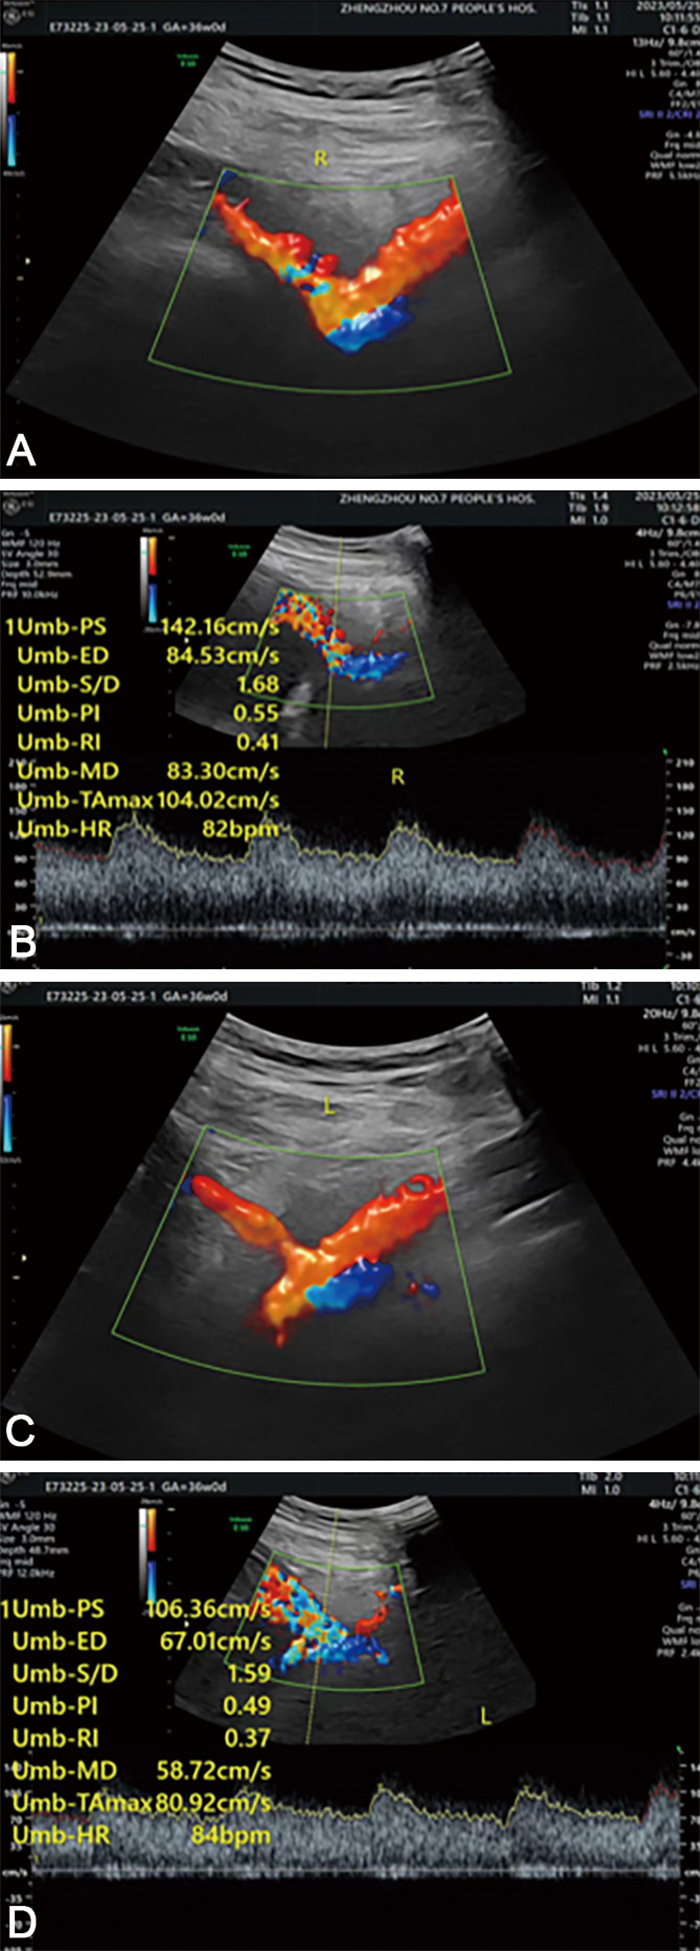

目的 早产(PTB)是新生儿死亡的主要原因,PTB风险较高的双胎孕妇胎盘屏障容易破裂,胎血流入母体,造成母体血清甲胎蛋白(AFP)水平升高。本研究探讨了子宫动脉血流参数联合AFP预测双胎早产的预测价值。 方法 选择2015年1月—2021年4月定期在郑州市第七人民医院产检的100例双胎妊娠孕妇进行回顾性分析,根据妊娠结局分为早产组(51例)和足月组(49例)。通过重复测量方差分析对比孕中期血清AFP水平和子宫动脉血流参数的差异,并且通过logistic回归分析研究二者对双胎妊娠早产结局的预测价值。 结果 随妊娠进展,早产组和足月组子宫动脉搏动指数(PI)、子宫动脉阻力指数(RI)、子宫动脉血流S/D值均逐渐下降,血清AFP水平均逐渐上升,早产组不同孕周子宫动脉血流动力学参数及血清AFP水平均高于同期足月组(P < 0.05)。血清AFP、PI、RI、S/D值及四者联合预测双胎早产的AUC分别为0.952、0.881、0.903、0.919和0.966。Logistic回归分析显示,血清AFP、PI、RI和S/D值是双胎孕妇早产的影响因素(OR值分别为2.746、1.262、1.509、2.158)。 结论 血清AFP水平、PI、RI和S/D值可以联合预测双胎早产,并且提高了单指标的灵敏度和特异度。 Abstract:Objective Preterm birth (PTB) is the main cause of neonatal death. Twins at high risk of PTB are susceptible to placental barrier rupture and fetal blood flow entering the mother, resulting in an increase in maternal serum alpha-fetoprotein (AFP) levels. The purpose of this study was to explore the predictive value of combining uterine artery blood flow parameters with AFP levels in predicting preterm delivery in twins. Methods A total of 100 pregnant women with twin pregnancy who underwent regular antenatal examination in the Seventh People' s Hospital of Zhengzhou from January 2015 to April 2021 were retrospectively analyzed. According to the pregnancy outcome, they were divided into a premature group (n=51) and a term group (n=49). Differences in mid-pregnancy serum AFP levels and uterine artery blood flow parameters were compared through repeated measurement analysis of variance. The predictive value of these factors for premature birth outcomes in twin pregnancies was assessed through logistic regression analysis. Results As progression of pregnancy, uterine artery pulsatility index (uterine artery pulsation index, PI), uterine artery resistance index (uterine artery resistance index, RI), and uterine artery blood flow Scarlett D value decreased, while serum AFP level increased gradually in both the preterm group and term group. The uterine artery hemodynamic parameters and serum AFP levels in the preterm group were higher than those in the term group at various gestational weeks. The AUC values of serum AFP, PI, RI, S/D and their combination were 0.952, 0.881, 0.903, 0.919 and 0.966, respectively. Logistic regression analysis showed that serum AFP, PI, RI and S/D were risk factors for preterm delivery in twin pregnant women (OR=2.746, 1.262, 1.509 and 2.158, respectively). Conclusion The combination of serum AFP levels, PI, RI, and S/D values can effectively predict premature delivery in twin birth, improving the sensitivity and specificity compared to single indicators. -

组别 例数 S/D 27~29周 30~32周 33~36周 早产组 51 9.42±1.24 9.12±0.47 8.78±0.29 足月组 49 5.43±0.53 5.21±0.58 5.03±0.37 F值 12.342 13.493 13.726 P值 < 0.001 < 0.001 < 0.001 组别 例数 PI 27~29周 30~32周 33~36周 早产组 51 2.62±0.07 2.38±0.36 2.13±0.45 足月组 49 1.95±0.35 1.84±0.27 1.80±0.16 F值 10.216 9.984 9.438 P值 < 0.001 < 0.001 < 0.001 组别 例数 RI 27~29周 30~32周 33~36周 早产组 51 0.78±0.09 0.73±0.05 0.69±0.18 足月组 49 0.55±0.11 0.56±0.15 0.53±0.03 F值 8.767 8.698 9.034 P值 < 0.001 < 0.001 < 0.001 组别 例数 AFP(μg/L) 27~29周 30~32周 33~36周 早产组 51 121.20±7.07 133.63±6.75 151.20±7.07 足月组 49 56.12±5.08 60.68±6.23 70.58±4.21 F值 24.325 29.549 26.839 P值 < 0.001 < 0.001 < 0.001 注:S/D,F时间=11.452,F组别=13.683,F交互=25.301,均P < 0.001;PI,F时间=12.654,F组别=10.935,F交互=15.368,均P < 0.001;RI,F时间=7.632,F组别=8.622,F交互=13.008,均P < 0.001;AFP,F时间=20.658,F组别=12.254,F交互=35.014,均P < 0.001。 表 2 各检测指标对于双胎早产的诊断效能